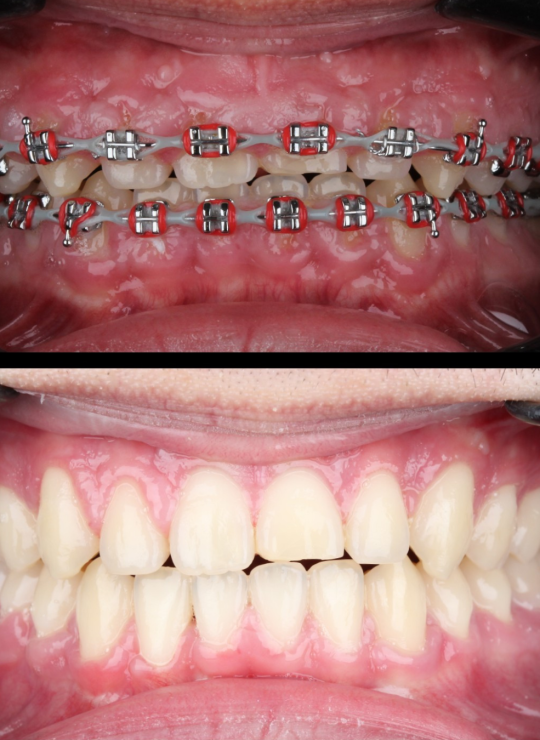

A Crown Lengthening Masterclass

Case demonstrations: gummy smile correction, uneven gingival margins, anterior restorative integration (veneers, crowns)

Integrating anterior and posterior protocols into daily practice